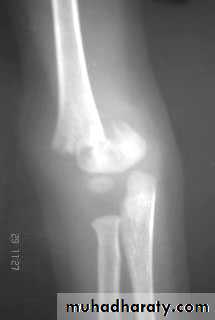

X-ray : the fracture is seen clearly in A-P , and lateral views . In undisplaced fracture the

fat-pad sign which is triangular lucency in front of the distal humerus this will raise the

suspicion of the fracture.

In A-P view we can measure the Boumans’ angle which is helpful in assessing the degree of angulation of the distal segment normally less than 80`.